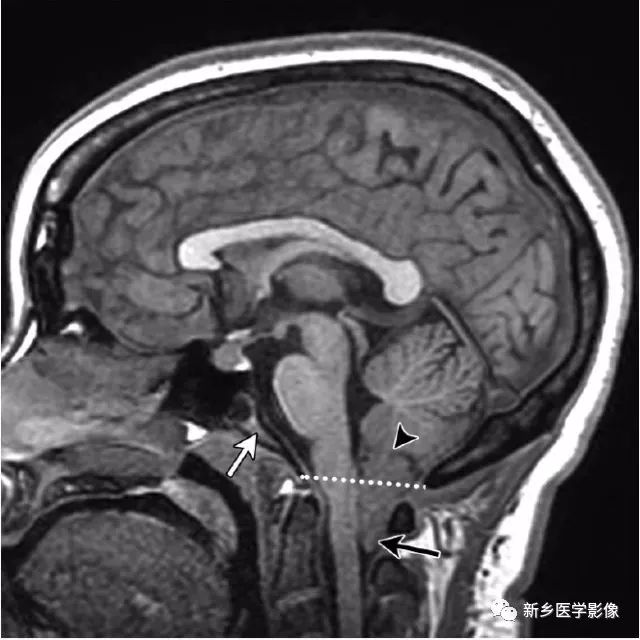

大脑中线处常见的25种疾病

大脑中线处常见疾病汇总